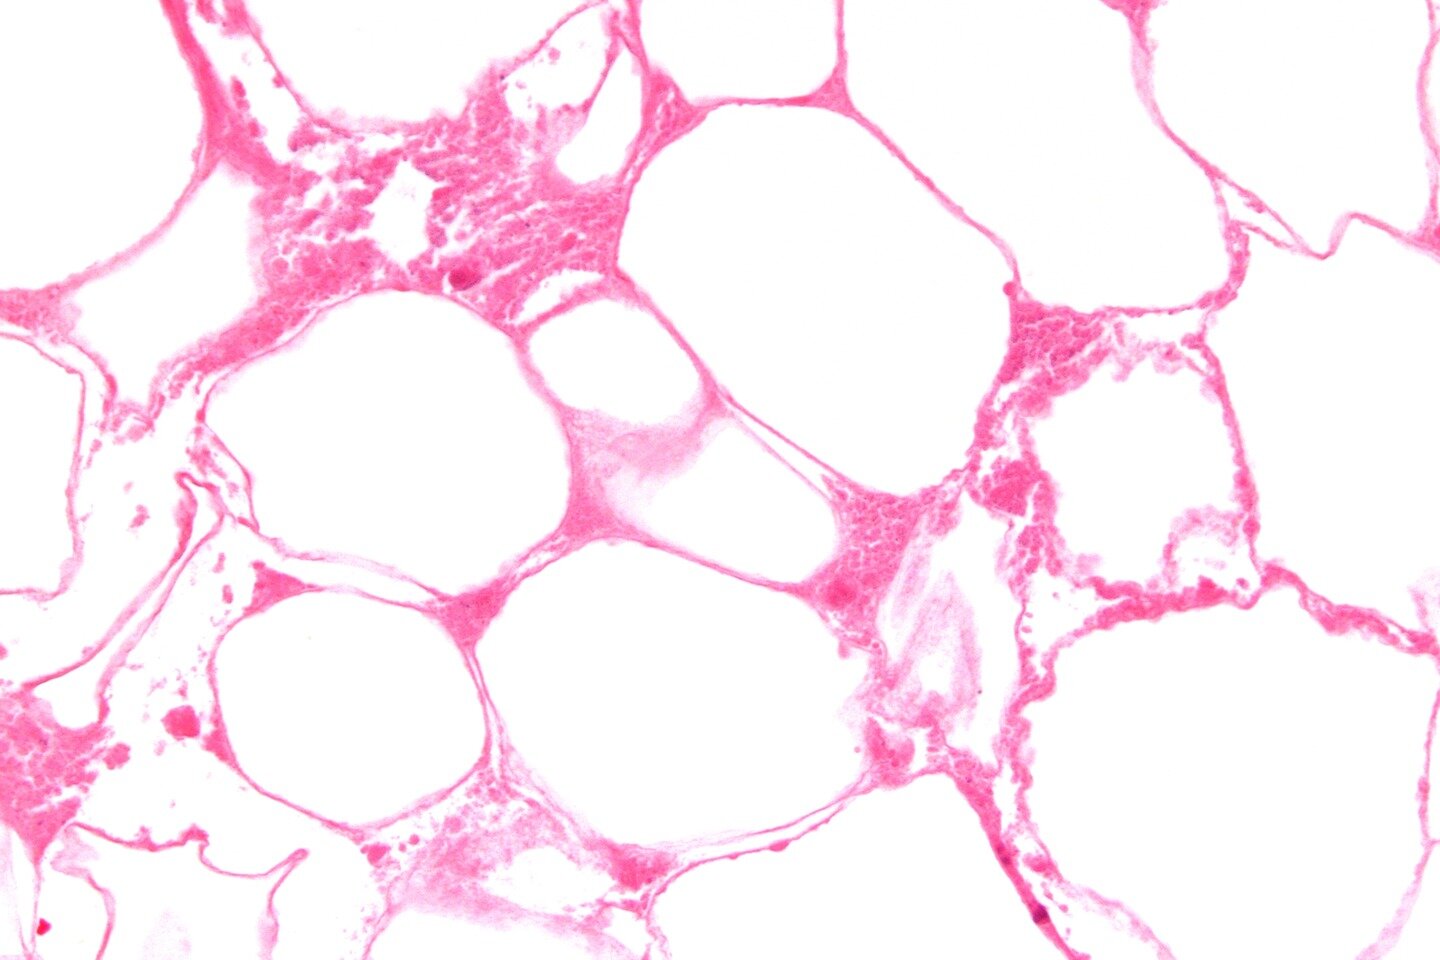

In this layer there are cells that receive the stimuli of pain, touch, pressure and temperature from the external environment. Their largest clusters are on the fingertips and on the lips. The subcutaneous layer is made of fat cells. Its thickness depends on the position in the body, the way of eating, lifestyle, gender. It protects deeply located tissues against mechanical injuries. It is also a thermal insulation layer, and a storage of chemical compounds.